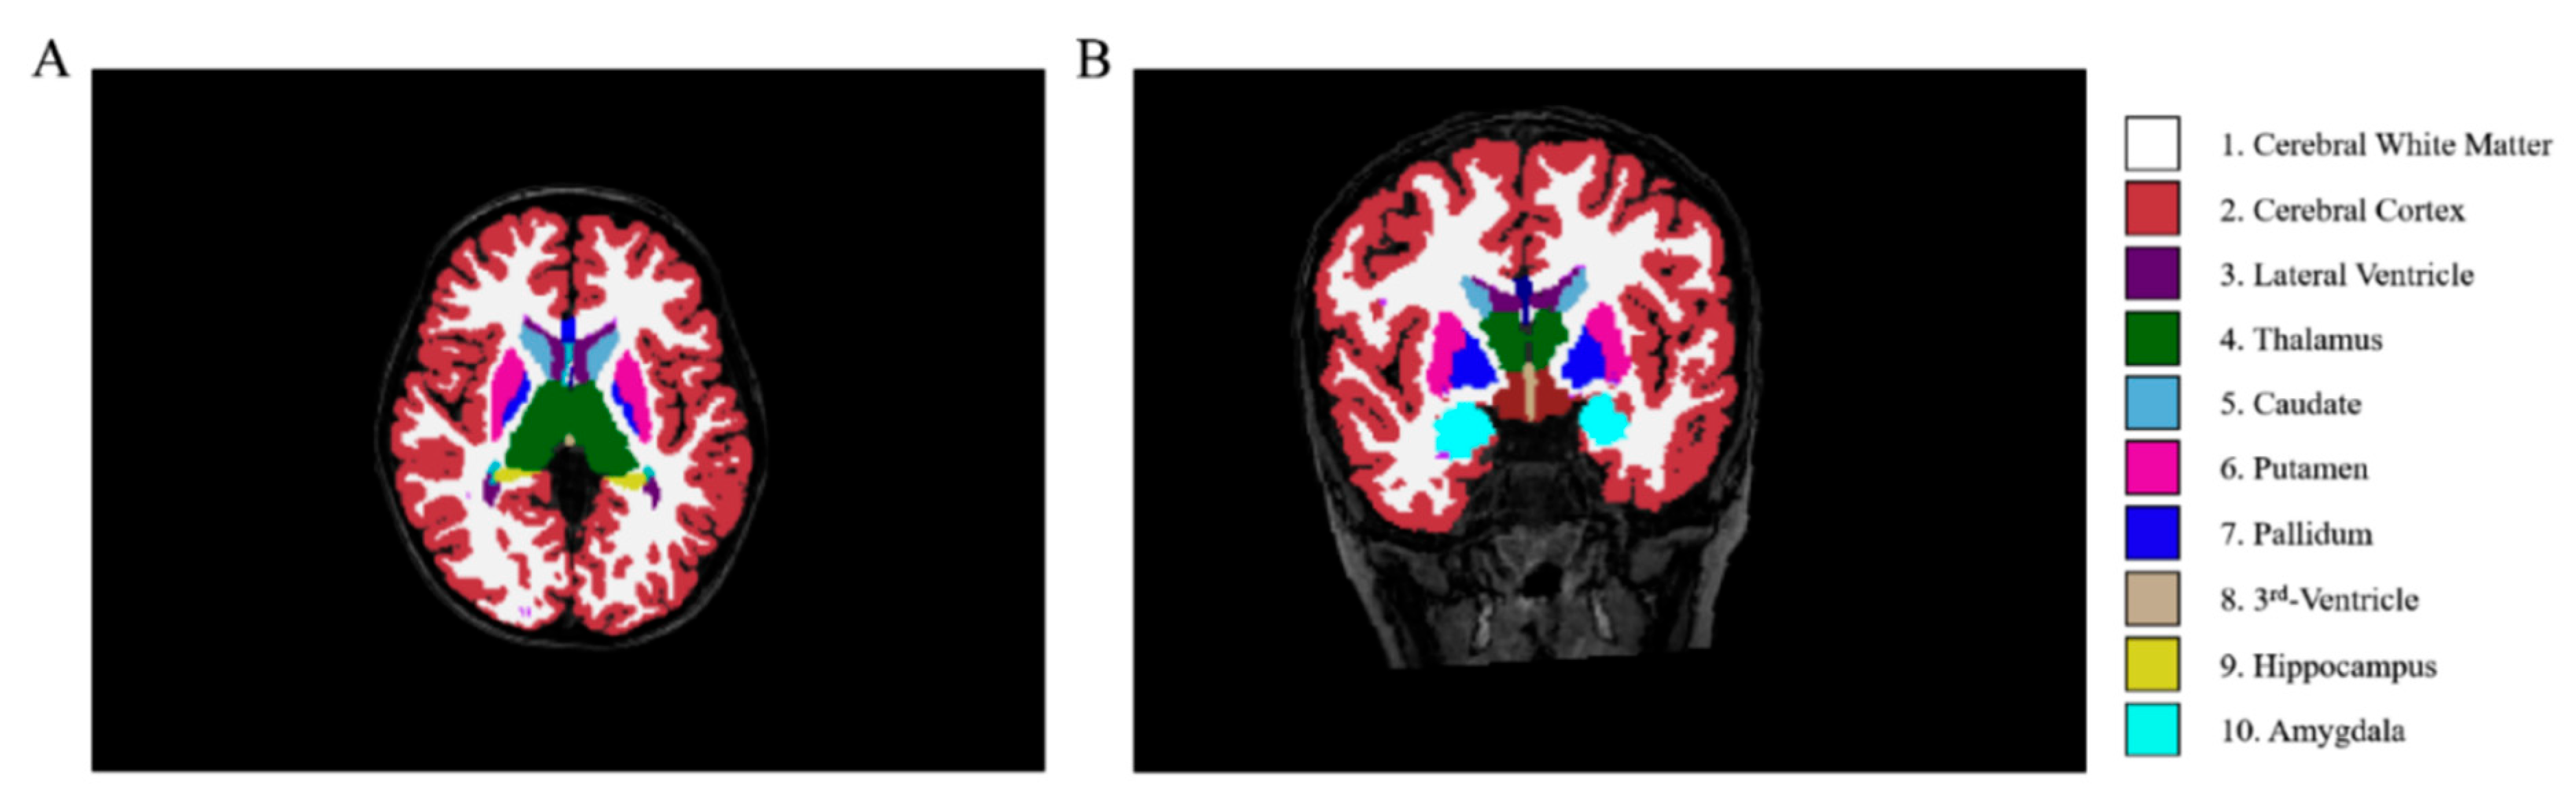

3D-T1WI images were processed with FreeSurfer v6.0 (https://surfer.nmr.mgh.harvard.edu, accessed on 22 August 2025) using the automated recon-all pipeline, and the quality of the preprocessed images was verified. The subcortical nuclei were segmented into 7 subregions (Fig. 2): left thalamus proper nucleus (LTHA), left amygdala nucleus (LAM), right thalamus proper nucleus (RTHA), right caudate nucleus (RCAU), right putamen nucleus (RPU), right pallidum nucleus (RPA), and right amygdala nucleus (RAM).

Figure 2: Schematic diagram of brain region segmentation results processed by FreeSurfer. (A) (axial view) and (B) (coronal view) display a 3D T1-weighted MRI scan with segmented subcortical structures. The color codes are as follows: cerebral white matter (1), cerebral cortex (2), lateral ventricle (3), thalamus (4), caudate (5), putamen (6), pallidum (7), third ventricle (8), hippocampus (9), and amygdala (10).; Note: Adapted from Ref. [19].